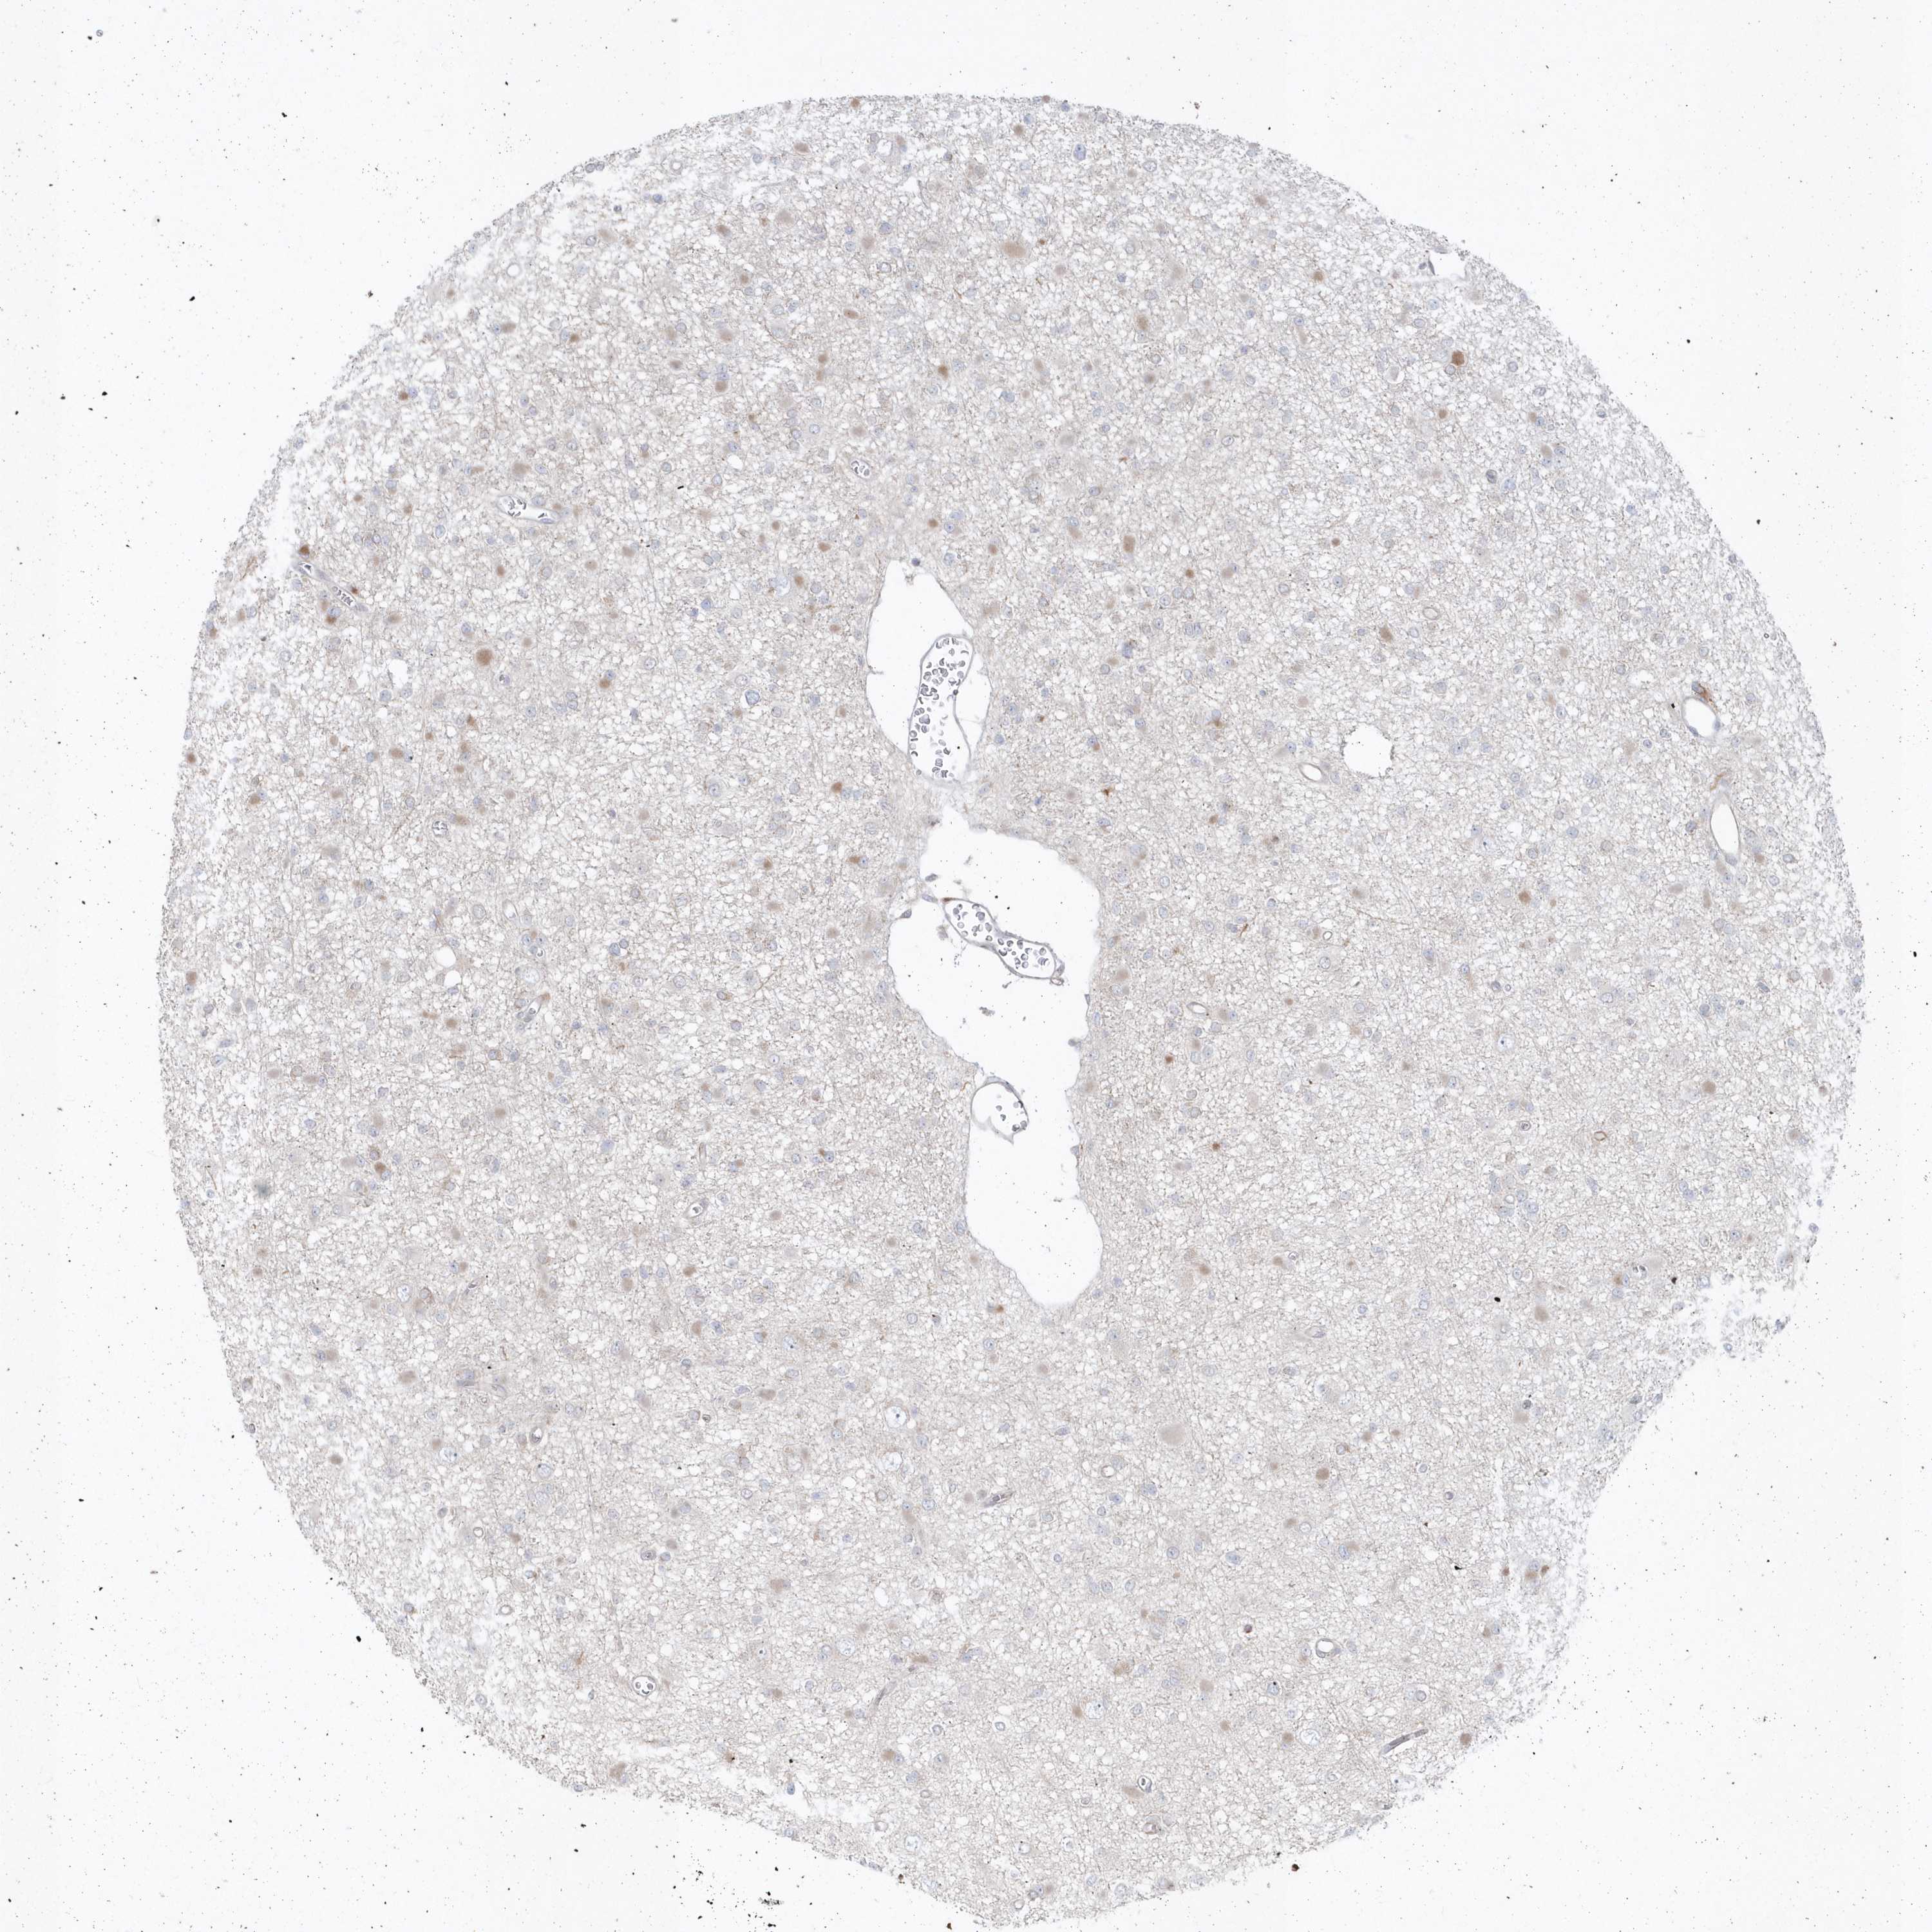

GLIOMA - Protein expressioni

A mouse-over function shows sample information and annotation data. Click on an image to view it in a full screen mode. Samples can be filtered based on level of antibody staining by selecting one or several of the following categories: high, medium, low and not detected. The assay and annotation is described here.

Note that samples used for immunohistochemistry by the Human Protein Atlas do not correspond to samples in the TCGA dataset.

Antibody stainingi

Antibody staining in the annotated cell types in the current human tissue is reported as not detected, low, medium, or high, based on conventional immunohistochemistry profiling in selected tissues. This score is based on the combination of the staining intensity and fraction of stained cells.

Each image is clickable and will lead to virtual microscopy that enables deeper exploration of all samples and also displays staining intensity scores, fraction scores and subcellular localization as well as patient and tissue information for each sample.

Antibody HPA036160

Staining

High

Medium

Low

Not detected

Intensity

Strong

Moderate

Weak

Negative

Quantity

>75%

75%-25%

<25%

None

Location

Nuclear

Cytoplasmic/membranous

Cytoplasmic/membranous,nuclear

Glioma, malignant, High grade

Glioma, malignant, Low grade

Glioblastoma, NOS